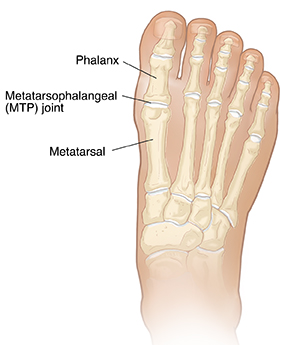

Your big toe joints

Your big toe has two joints. The metatarsophalangeal (MTP) joint is the largest. This is where the first long bone of the foot (metatarsal) connects with the first bone of the toe (phalanx). Strong tissues surround this joint and hold it in place. These include:

Fibrous tissues under the MTP joint.

Ligaments on the sides of your big toe.

A tendon that runs under the first metatarsal bone.

Two tiny bones that help this tendon move.